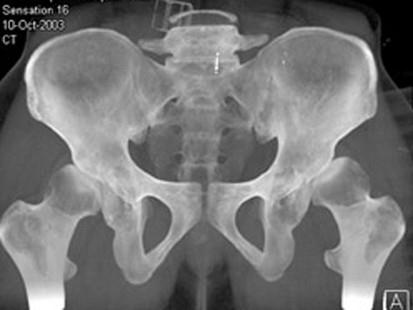

问题 男,23岁,行走跛行,外展受限,两下肢不等长,结合图像,最可能的诊断是 ( )

选项 A、先天性髋内翻 B、髋关节结核 C、髋关节后脱位 D、髋关节前脱位 E、髋关节中心脱位

答案 C